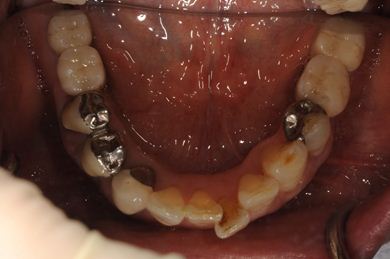

治療前

• 治療前